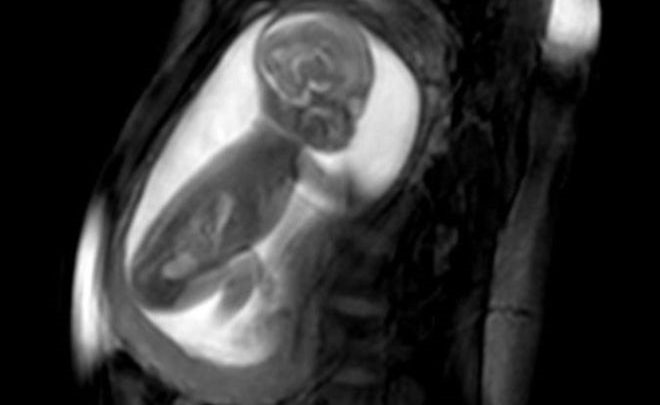

تقنية جديدة لتصوير قلوب الأجنة تساعد في إنقاذ حياة الأطفال فور الولادة

نجح باحثون في التقاط صور غير مسبوقة لقلب جنين وهو ينبض داخل رحم الأم، ما ساعد في تشخيص أمراض القلب وعلاجها فور ولادة الطفل.

وفحصت النساء الحوامل بجهاز تصوير الرنين المغناطيسي وأجهزة كمبيوتر فعالة تستطيع رسم نماذج ثلاثية الأبعاد لقلوب الأجنة الصغيرة النابضة في رحم أمهاتها.

ويلتقط الباحثون سلسلة صور ثنائية الأبعاد للقلب من زوايا مختلفة باستخدام جهاز التصوير بالرنين المغناطيسي، لكن قلب الجنين صغير للغاية، وينبض بسرعة مذهلة، كما أن الجنين يتحرك داخل الرحم لذلك فإن تصوير القلب يبدو غير واضح تماما، لكن جاءت هذه الأداة الذكية لتصنع الفارق حقا.

وتستطيع برامج الكمبيوتر المتطورة جمع الصور معا، وضبطها من خلال ضربات القلب ثم إنشاء صورة ثلاثية الأبعاد غير مسبوقة للقلب بالكامل، ومن ثم فهي تقدم للأطباء رؤية واضحة للخلل في القلب.